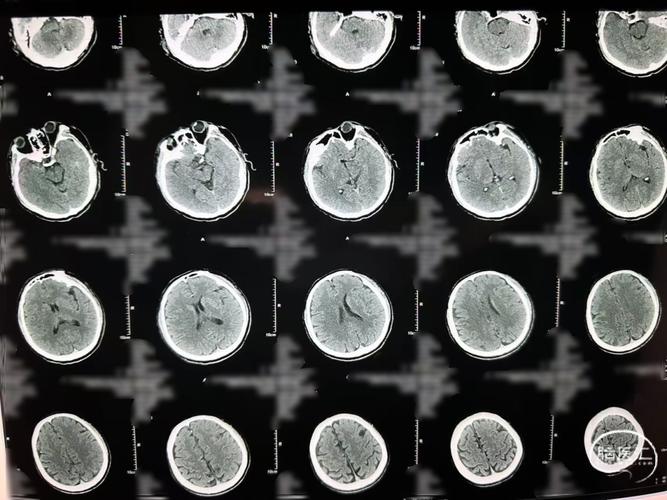

脑梗塞在CT影像上的表现,取决于梗塞灶的病理变化过程,这个过程需要时间。

超早期(发病0-6小时内):CT可能完全正常

在这个阶段,脑组织因为缺血缺氧已经开始出现问题,但细胞结构还没有发生足以被CT分辨的密度改变,CT上可能看不到任何异常,或者只能看到一些非常不特异的微小变化,容易被忽略。

早期(发病6-24小时内):CT开始出现细微变化

梗塞灶的中心区域开始发生“细胞毒性水肿”,细胞体积增大,导致局部脑组织密度出现轻微变化,但这个变化非常细微,经验不足的放射科医生也可能难以识别,一些先进的CT技术(如CT灌注成像)可以帮助发现早期缺血,但这不是常规的平扫CT。

确诊期(发病24-48小时后):CT显示清晰梗塞灶

这是脑CT诊断脑梗塞的“黄金时间”。

- 病理变化: 梗塞区域的脑细胞开始死亡、崩解,细胞结构被破坏,水分含量显著增加,形成“血管源性水肿”。

- CT影像表现: 在CT图像上,这个区域会呈现出低密度的暗影,因为正常的脑组织密度与脑脊液接近,而梗塞后的组织密度会进一步降低,像一块“被泡发了的脑组织”,与周围正常脑组织形成鲜明对比,诊断脑梗塞就非常明确了。

慢性期(发病数周至数月):CT表现更典型

- 影像变化: 梗塞灶的脑组织会发生液化、坏死,最终形成一个脑软化灶,在CT上,这会是一个边界清晰、永久性的低密度区,其内部甚至可能因为脑组织萎缩而出现与脑脊液密度完全相同的囊腔。